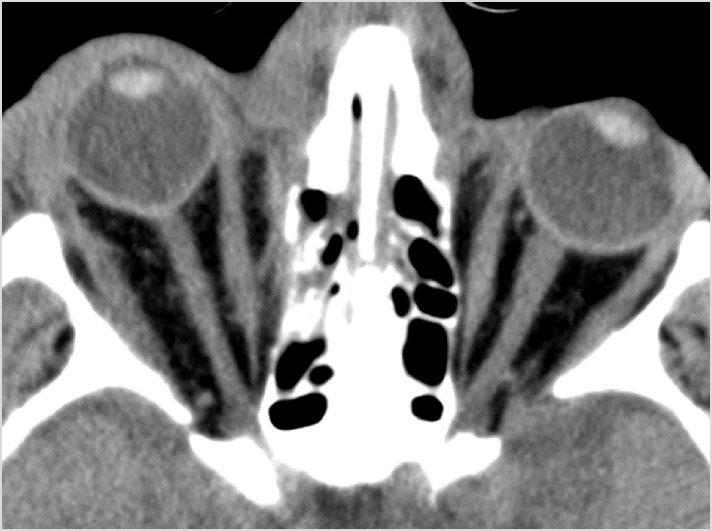

Orbits and Orbital Zygomatic Complex

There is evidence of bony injury along the walls and/or floor of the orbit.

Fronto-Naso-Ethmoidal Complex

The mesial naso-orbito-ethmoid complex is fractured. Specifically, there is bony injury of the nasal bones or the frontal process of the maxilla and the medial walls of the orbit are abnormal.